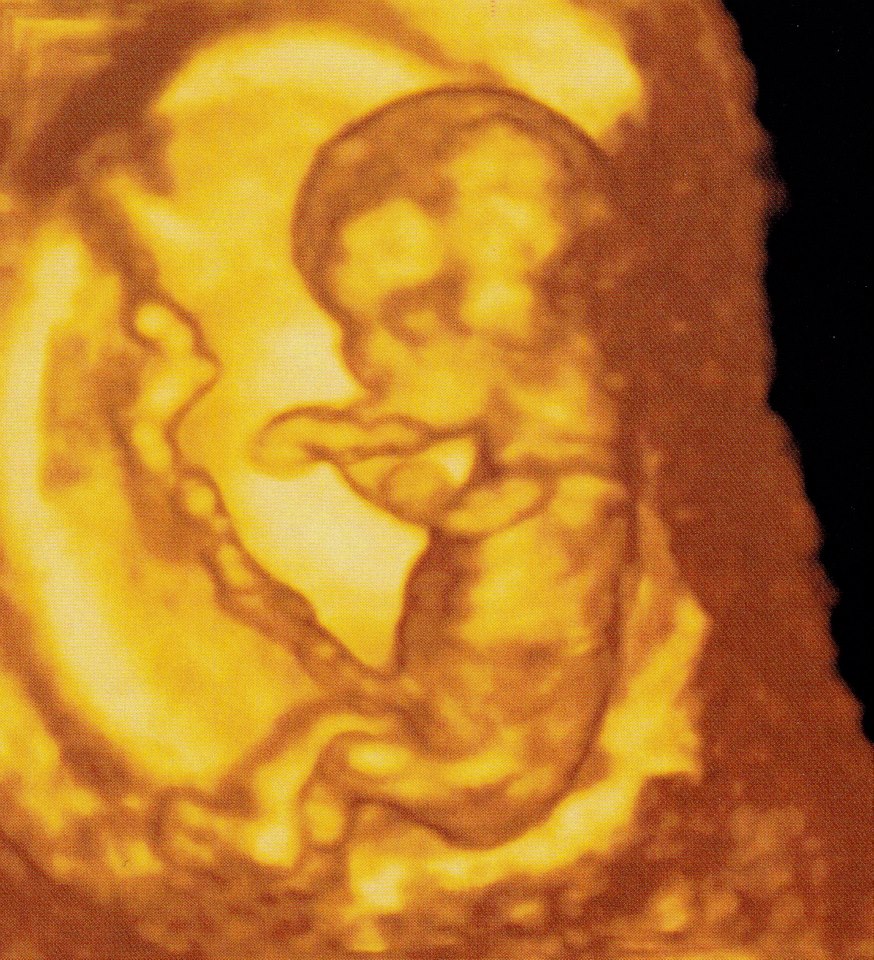

girl 3d pics are amazing

I am also leaning boy. The nub is flattish but the angle is upward. Also, the b/w pic has a boyish skull and nub.

Thanks everyone - do u know how accurate skull theory is? so many theories out there. I know this baby is attached to left side which ties in with another theory, nub theory has guessed 50 girls against 4 boy comments with 3 ultrasound techs guessing girl . I took urine test and came back girl. this is going to be an interesting outcome in 17 days :) as I will post results...